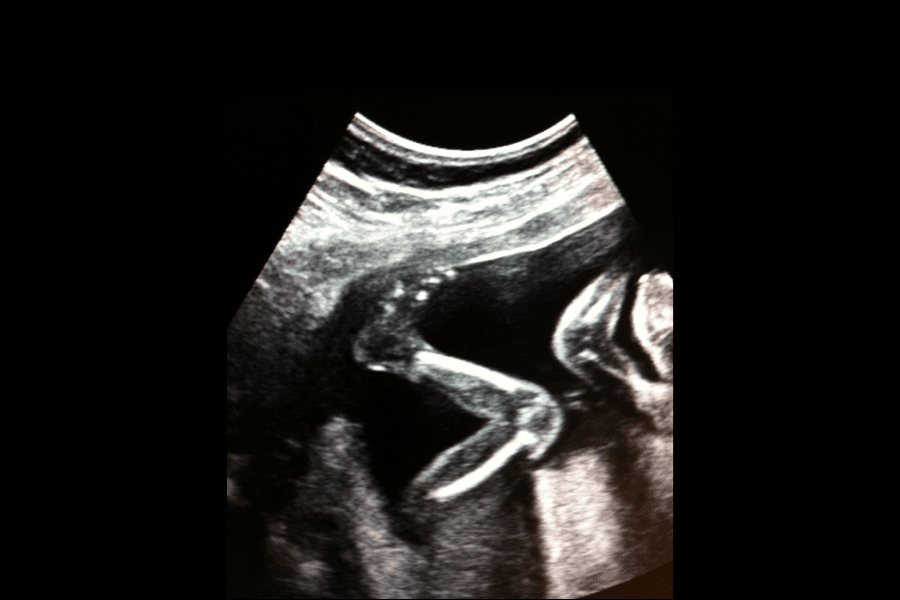

El movimiento de cada bebé en el útero es diferente; cada bebé se mueve de manera individual y en momentos diferentes. El bebé hace incluso pequeños movimientos que son difíciles, o imposibles, de percibir. Da patadas, practica cómo respirar y tragar, y el reflejo de prensión y succión. No todos los movimientos son patadas.

La manera de sentir las movimientos del bebé dependerá de su personalidad, el espacio que tenga y de la posición en la que esté en el útero, y también de la ubicación de la placenta.

Identificar el patrón de movimiento de un bebé activo es, por supuesto, más fácil. La posición del bebé en el útero podría afectar la intensidad con la que la madre siente los movimientos. Será más fácil sentir cuando da patadas hacia fuera que si da patadas hacia adentro del útero, contra la columna vertebral de la madre.